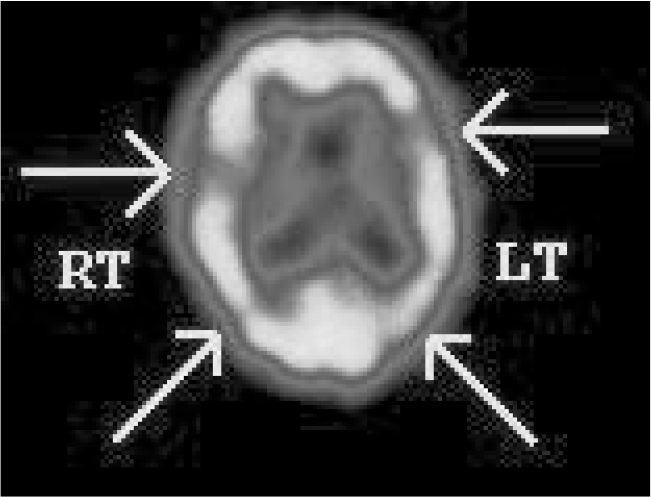

Single-photon emission computed tomography findings in Alzheimer’s disease centre on the detection of hypoperfusion of the temporal and parietal brain regions (Reference Kantarci and JackKantarci 2003) (Fig. 1).Reference Jagust, Thisted and DevousJagust et al (2001) compared clinical diagnosis, SPECT findings and post-mortem examination and found that SPECT increased the diagnostic certainty in patients who were clinically diagnosed with Alzheimer’s disease from 84 to 92%. This study found that a negative SPECT in these patients reduced the diagnostic certainty to 70%.

FIG 1 Tc-99m HMPAO single-photon emission computed tomography findings in a patient with clinical dementia. The scan shows reduced perfusion in the left frontotemporal, right temporal, left parietal and right parietal lobes. These findings suggest Alzheimer’s disease.